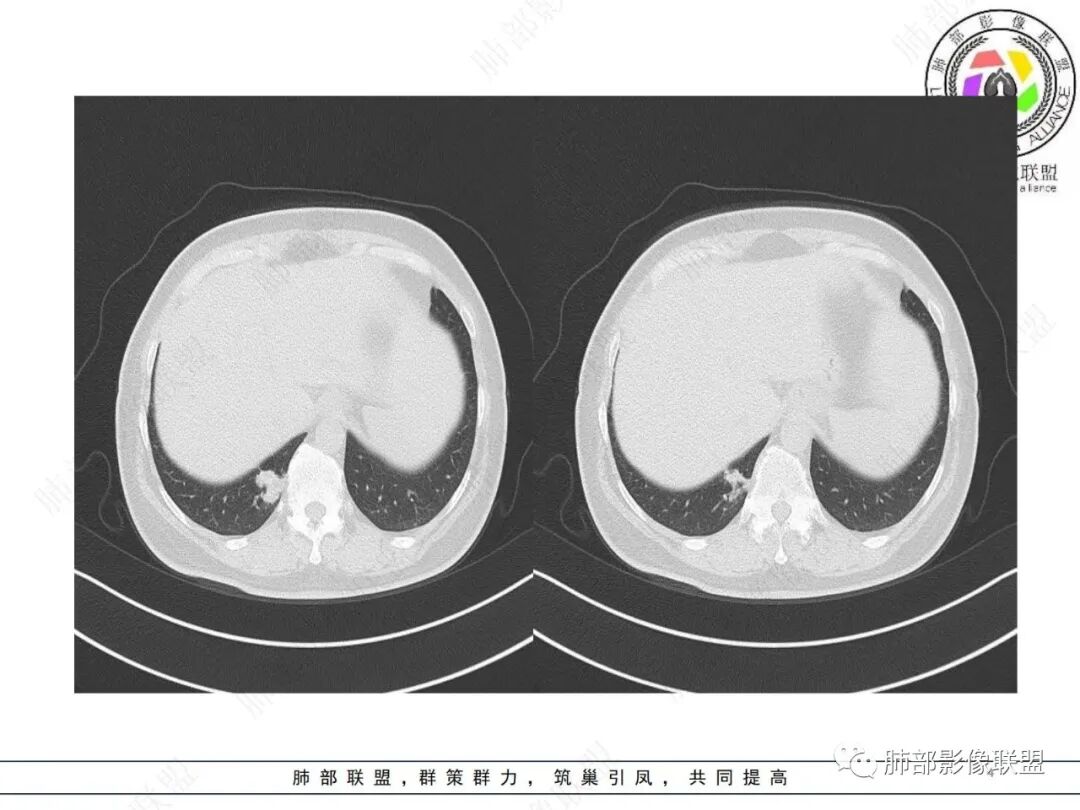

中年女性,右肺下叶后基底段胸膜下不规则稍低密度结节影,内见多发钙化,边缘部分平直,邻近胸膜下脂肪间隙清晰,增强扫描呈均匀轻中度强化,病灶边缘见少许小斑片状影,考虑良性病变,炎性肉芽肿可能,鉴别错构瘤

右肺下叶后基底段结节,形态不规则,有分叶和毛刺,内可见爆米花样钙化,实性成分有强化,绿色无坑肯定考虑错构瘤,晨读估计不会这么简单,所以考虑腺癌?转移性腺癌?鉴别结核

中年女性 右肺下叶不规则实性病灶中心伴钙化,边缘有分叶、胸膜线样牵拉,增强后中等强化,常规思路考虑良性病灶,但是如果有老片 持续观察这个病灶 是否是在增大,腺癌还是可能的,有的肺癌可伴发钙化就是密度没有这么高,疤痕基础上发生也有可能。

右肺下叶胸膜下不规则结节,分叶,其内爆米花样钙化,轻度强化,考虑错构瘤,鉴别腺癌

中年女性,无临床症状,胸部CT右肺下叶基底段实变影,边缘清楚,部分边缘刀切征,中间大部分钙化,局部胸膜无侵犯,似乎可见支气管充气征,考虑炎性肉芽肿,错构瘤待排

这个形态还是像腺癌,有膨隆有分叶,边缘磨玻璃边界清,非钙化部分轻度强化。腺癌可以钙化的,估计是干扰项

右肺下叶分叶状实性结节伴钙化,胸膜牵拉似有侵犯,增强后轻度强化,倾向恶性,腺癌可能。

右肺结节,边界清楚,中心钙化,钙化边缘模糊,轻度强化,考虑腺癌,鉴别错构瘤。

右肺下叶内基底段胸膜下分叶状肿块,边界清,密度不均匀,有成簇状钙化(与错构瘤钙化不同),实性部分有强化,肿块边缘凹陷明显(有收缩力),周围集血管束特点,方向首选肺肿瘤,考虑肺腺Ca。